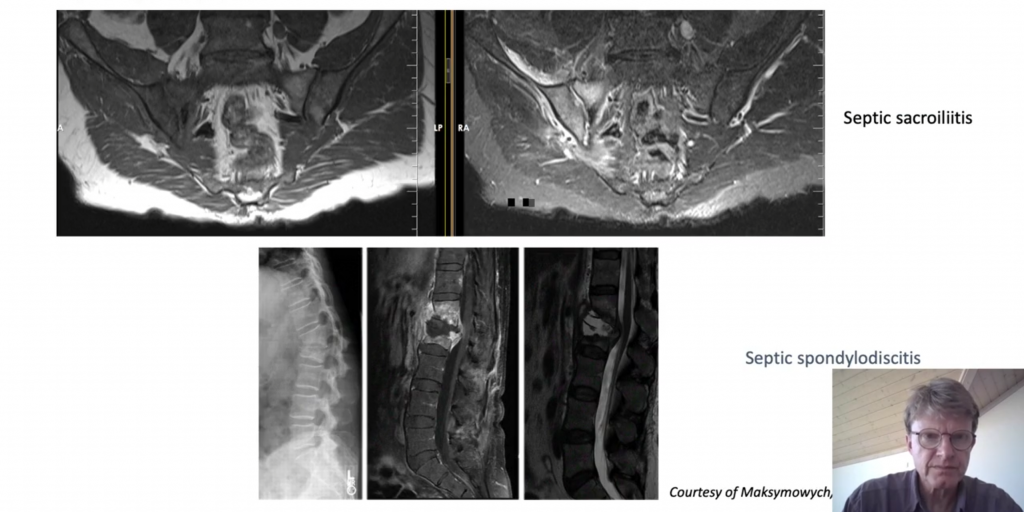

Differential diagnoses in suspected axial SpA

What should we look for on MRI in the sacroiliac joints, and what is and what is not sacroiliitis? These questions and other relevantes, will be answered in this MEDtalk by Mikkel Østergaard, professor, Copenhagen Center for Arthritis Research (COPECARE), Rigshospitlet, Glostrup and University of Copenhagen, Denmark.